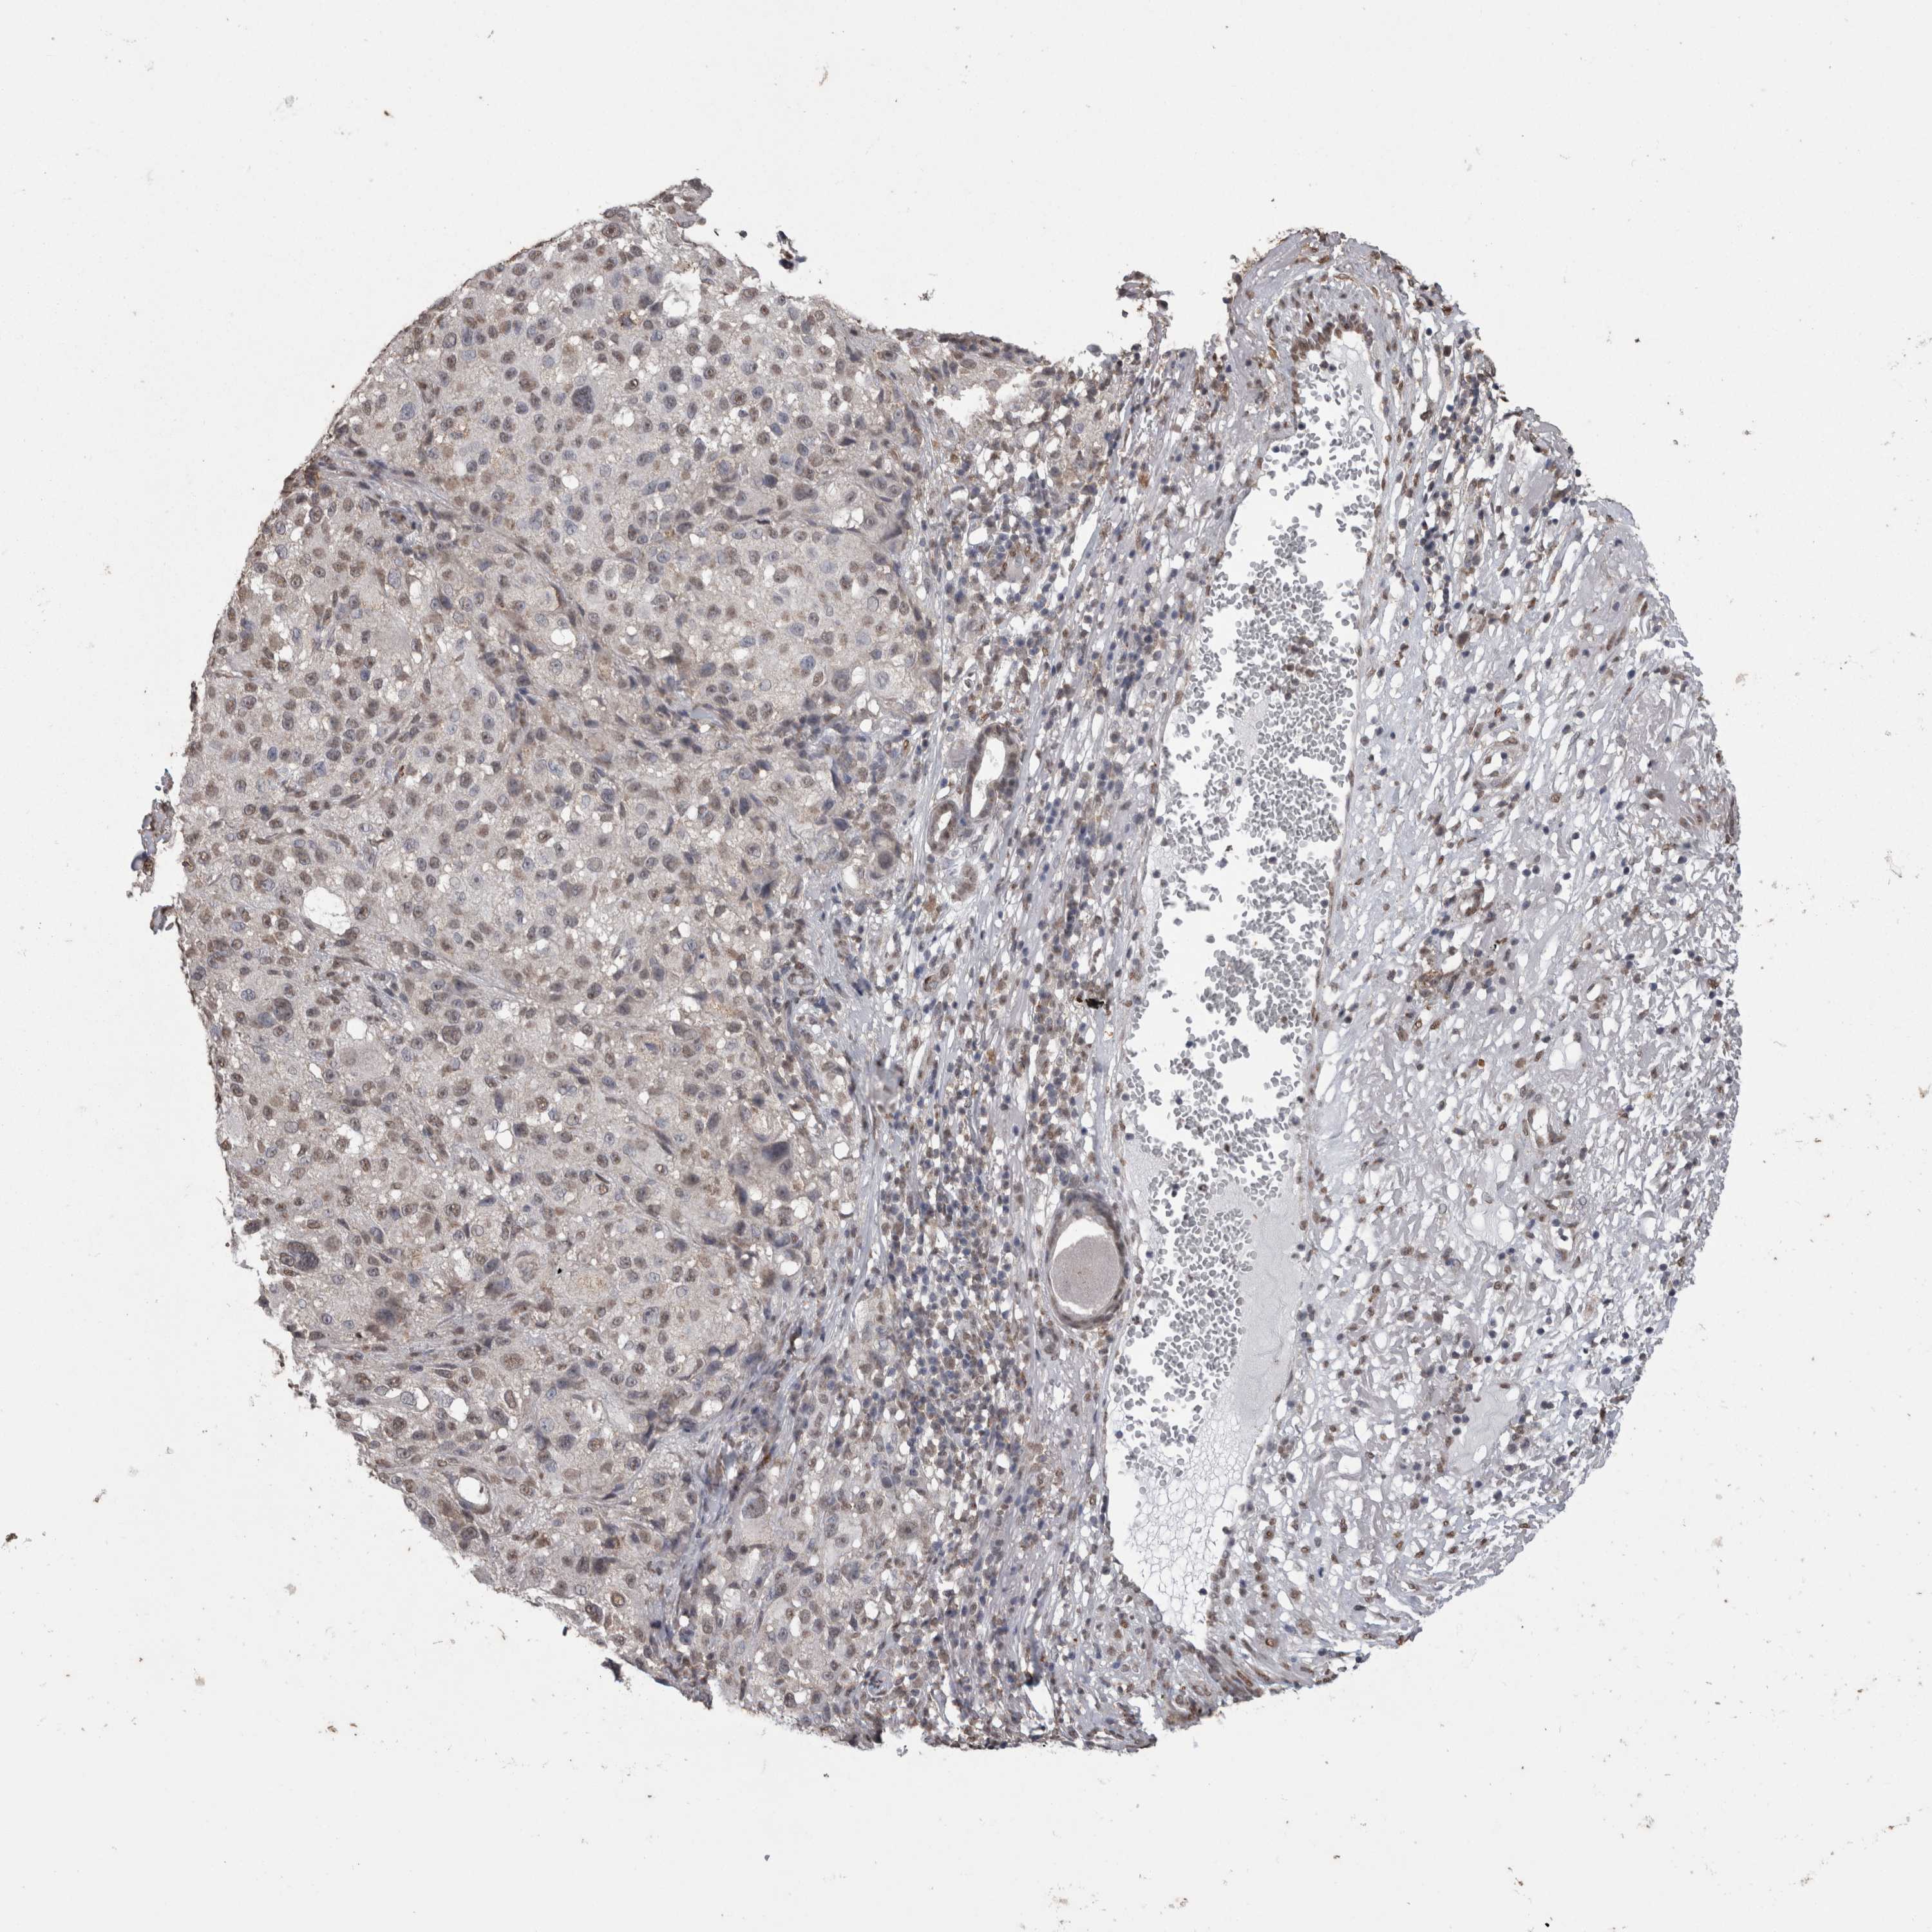

MELANOMA - Protein expressioni

A mouse-over function shows sample information and annotation data. Click on an image to view it in a full screen mode. Samples can be filtered based on level of antibody staining by selecting one or several of the following categories: high, medium, low and not detected. The assay and annotation is described here.

Note that samples used for immunohistochemistry by the Human Protein Atlas do not correspond to samples in the TCGA dataset.

Antibody stainingi

Antibody staining in the annotated cell types in the current human tissue is reported as not detected, low, medium, or high, based on conventional immunohistochemistry profiling in selected tissues. This score is based on the combination of the staining intensity and fraction of stained cells.

Each image is clickable and will lead to virtual microscopy that enables deeper exploration of all samples and also displays staining intensity scores, fraction scores and subcellular localization as well as patient and tissue information for each sample.

Antibody HPA028897

Antibody CAB026212

Staining

High

Medium

Low

Not detected

Intensity

Strong

Moderate

Weak

Negative

Quantity

>75%

75%-25%

<25%

None

Location

Nuclear

Cytoplasmic/membranous

Cytoplasmic/membranous,nuclear

Malignant melanoma, NOS

Malignant melanoma, Metastatic site